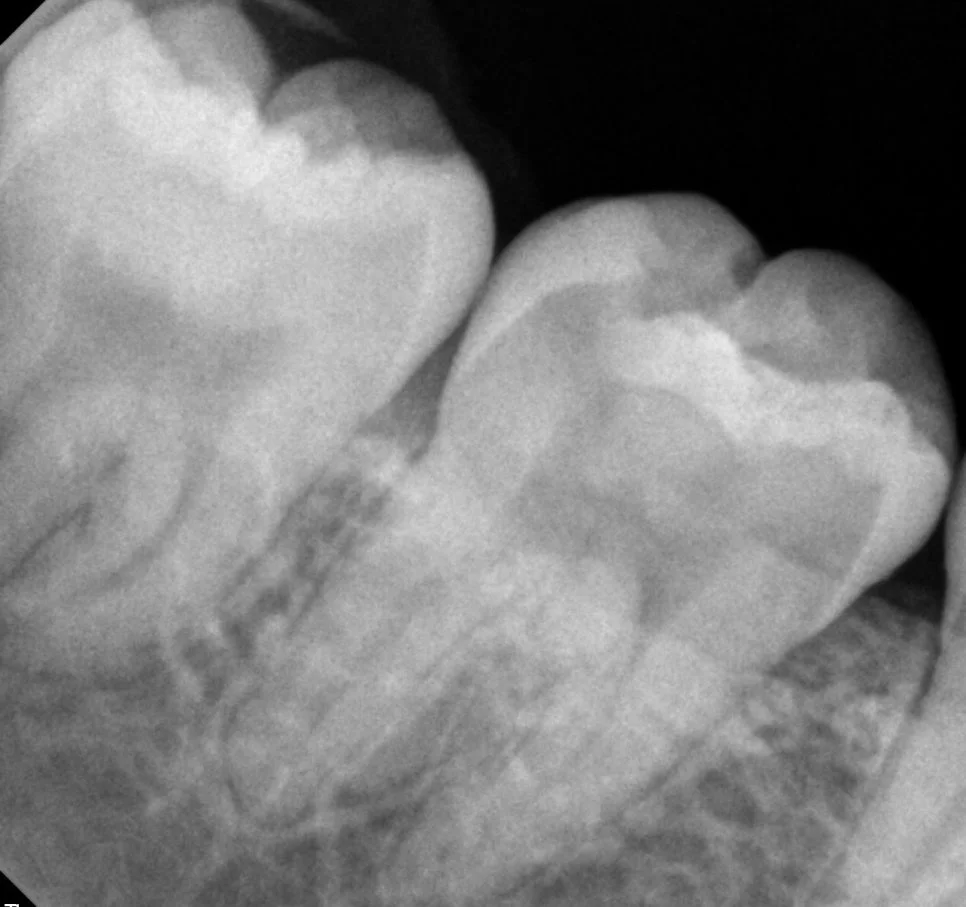

케이스2 우측 매복 사랑니 제2대구치 위협

우측 하악 매복 사랑니 — 제2대구치 바깥 면을 위협하는 가장 고난도 케이스

오른쪽 아래 매복 사랑니는 제2대구치의 바깥 면을 위협하고 있어 가장 난도가 높지만 빠르게 발치를 해줘야 하는 상태입니다.